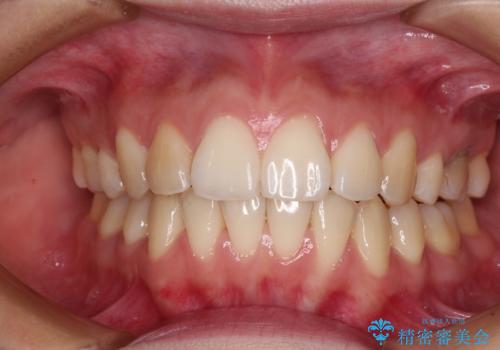

後戻りをインビザラインでスッキリした口元に

- 高校生の時に矯正治療を行ったものの、後取りをしてしまったとのことで来院された患者様です。

マウスピースでもワイヤー矯正でも対応可能でしたが、再度ワイヤーは装着したくないとのことでインビザラインにて矯正治療を行うこととしました。

舌の突出癖が原因で後戻りをしたため、舌のトレーニングをしっかりと行っていただき、口元の突出感を改善することができました。

インビザラインの装着時間が守れず、1年強で終わる予定でしたが、4年間を要することとなりました。